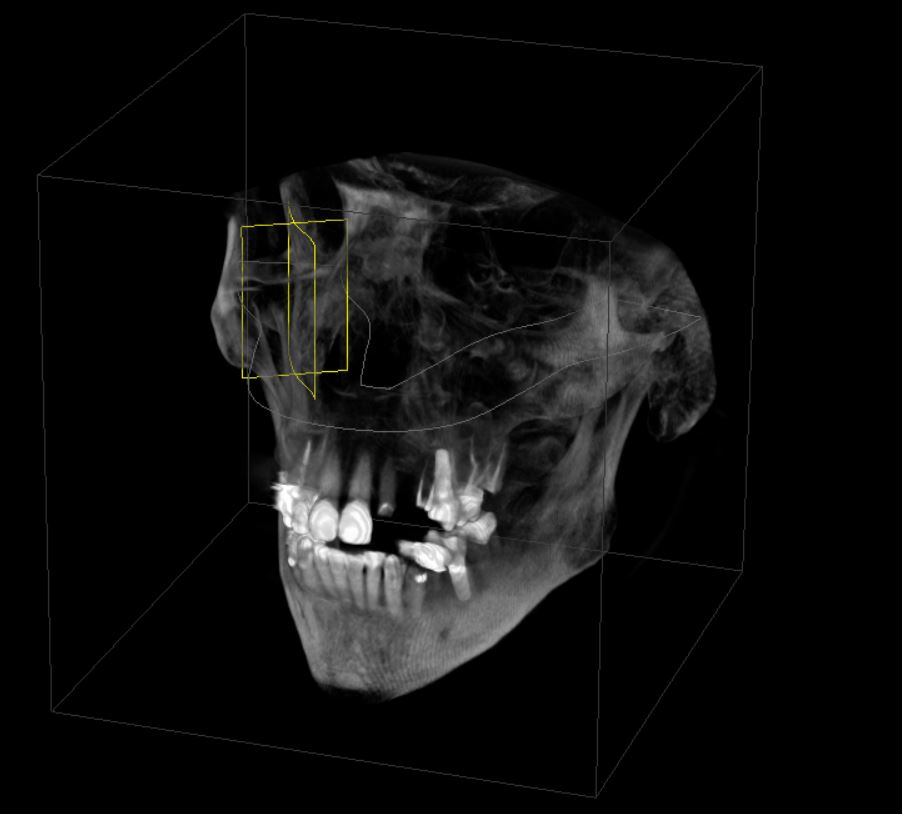

Full Arch Implant Planning Set Up with Medit i700

This used to be such a long process and we can bust them out in no time. take upper and lower scans in a minute. add lip…